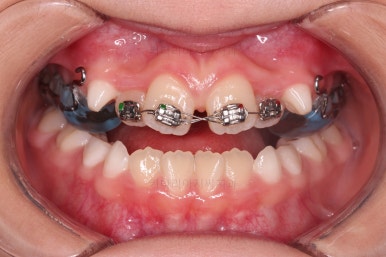

치료 종료!

총 13개월 걸려서 부산초등학생교정 위턱의 3차원적 성장과 앞니 가지런함을 다 이뤘어요.

앞니의 반대교합 뿐만 아니라 어금니 반대교합도 개선되었네요.

부산초등학생교정 전후 비교를 해보겠습니다.

부산초등학생교정 전후 모습을 보면 말 그대로 드라마틱한 변화네요.

특히 웃을 때 아랫니가 툭 튀어나와서 아랫니 위주로 보이던 미소가 완벽히 개선되어서 웃는 모습이 참 예뻐졌어요.

보호자분이 원하던 주걱턱도 개선되었고 초등학생 어린이 본인이 원하던 앞니 가지런함도 매우 좋아졌어요.